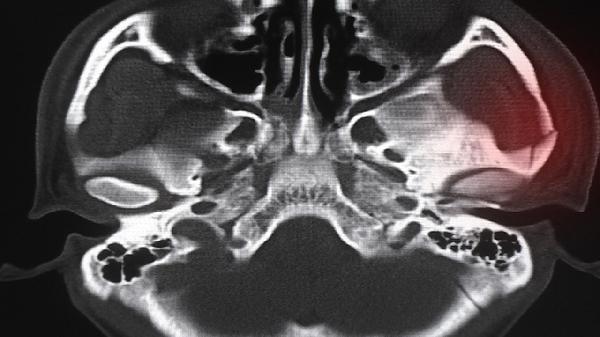

骨髓炎是骨骼感染性疾病,常由細(xì)菌通過(guò)血液傳播或直接侵入引起。感染會(huì)導(dǎo)致骨質(zhì)破壞、局部膿液形成,并可能形成難以愈合的竇道。治療關(guān)鍵在于徹底清除感染病灶,包括手術(shù)清創(chuàng)去除壞死骨組織,同時(shí)配合足量足療程的敏感抗生素治療。感染控制后,骨骼修復(fù)與軟組織再生需要數(shù)月至數(shù)年時(shí)間,期間需要維持良好的局部血運(yùn)與營(yíng)養(yǎng)支持。患者可能經(jīng)歷反復(fù)傷口滲液、骨質(zhì)缺損修復(fù)等階段,需要定期換藥與影像學(xué)評(píng)估。骨髓炎愈合受患者年齡、基礎(chǔ)疾病、感染部位及治療依從性影響。兒童因成骨能力較強(qiáng)通常預(yù)后較好,而糖尿病患者因微循環(huán)障礙可能面臨愈合延遲風(fēng)險(xiǎn)。

骨髓炎患者應(yīng)保持傷口清潔干燥,避免受壓或二次損傷。飲食需加強(qiáng)優(yōu)質(zhì)蛋白與維生素C攝入,如魚(yú)肉、雞蛋及新鮮蔬果,促進(jìn)組織修復(fù)。嚴(yán)格遵醫(yī)囑完成抗生素療程,不可自行停藥。定期復(fù)查X線或核磁共振觀察骨愈合情況,配合康復(fù)訓(xùn)練維持關(guān)節(jié)功能。出現(xiàn)紅腫加劇、發(fā)熱或膿液增多時(shí)需立即就醫(yī)。長(zhǎng)期吸煙與血糖控制不佳會(huì)顯著影響愈合,需積極調(diào)整生活習(xí)慣。骨髓炎康復(fù)是系統(tǒng)過(guò)程,需要醫(yī)療干預(yù)與日常護(hù)理相結(jié)合,患者需保持耐心并密切配合治療。